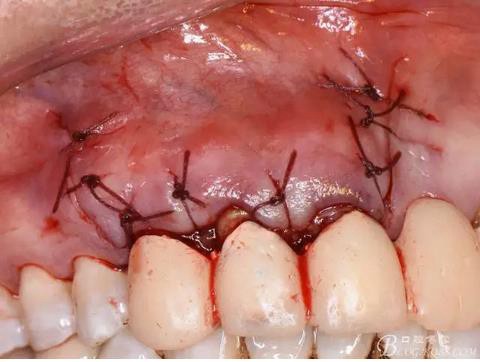

圖15.取愛如特生物陶瓷材料

圖16.放置在干燥好的根管內

圖17.根尖倒充填完畢

圖18.骨腔填塞膠原蛋白海綿

圖19.縫合